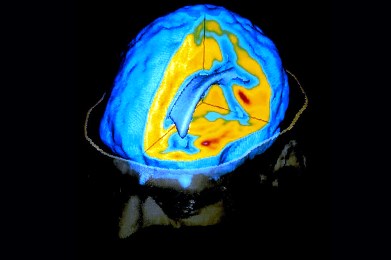

Τεχνολογία διαβάζει τα όνειρα με ακρίβεια 60% με αλγόριθμους και απεικόνιση του εγκεφάλου

Επιστήμη και τεχνολογία δεν σταματούν να διευρύνουν τόσο τα εσωτερικά όσο και τα εξωτερικά σύνορα της ανθρώπινης αντίληψης. Μετά την κατάκτηση του διαστήματος, ερευνητές ανέπτυξαν μια τεχνολογίαπου επιτρέπει την ανάγνωση των ονείρων που βλέπουμε κατά τη διάρκεια του ύπνου (και που συχνά ξεχνάμε όταν ξυπνάμε το πρωί). Ιάπωνες επιστήμονες κατασκεύασαν μια μηχανή “ανάγνωσης ονείρων” η οποία προβλέπει σε αδρές γραμμές, με ποσοστό ακρίβειας 60%, τις εικόνες που βλέπουν οι άνθρωποι κατά τη διάρκεια του ύπνου. Για την αποκωδικοποίηση των οπτικών δεδομένων που παράγει ο εγκέφαλος την ώρα του ύπνου που, χρησιμοποιήθηκε ένας μαγνητικός τομογράφος (MRI), μαθηματικά μοντέλα και εικόνες από το διαδίκτυο. Οι ερευνητές υποστηρίζουν ότι η επιτυχία τους έγκειται στην ανακάλυψη της διασύνδεσης μεταξύ...